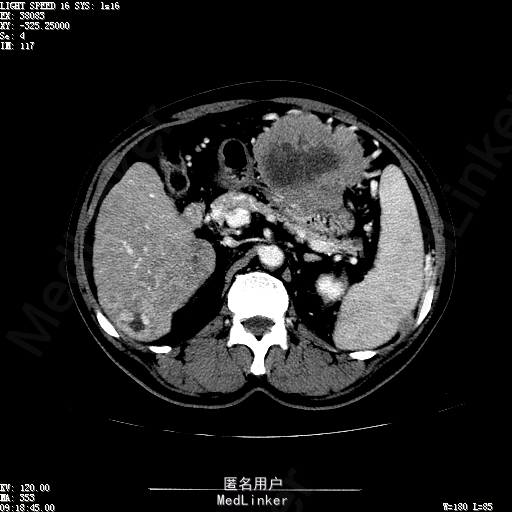

查体:生命体征平稳,神志清晰,发育正常,营养中等,体位自如,表情安静,无面容,配合检查合作。皮肤粘膜颜色正常,腹型平坦,无腹壁静脉曲张,未见胃肠型及蠕动波,无瘢痕,脐部正常。触诊:无压痛,无反跳痛,无腹肌紧张,无腹部包块。肝未触及,Murphy征阴性,脾未触及,肾未触及,无移动性浊音。 化验回报:血细胞分析(五分类):*白细胞计数 4.6 10^9/L、红细胞计数 4.27 10^12/L、血小板计数 100.0 10^9/L、血红蛋白 145 g/L、中性粒细胞百分比 68.6 %,*葡萄糖测定:葡萄糖 5.99 mmol/L,血清离子测定:*钾 4.46 mmol/L、钠 143.5 mmol/L,肾功能检测:*尿素 6.86 mmol/L、肌酐 84.2 umol/L,凝血五项:凝血酶原时间 10.7 秒、凝血酶原百分活动度 93.3 %,乙肝六项:乙型肝炎病毒表面抗原 阳性(+) 、乙型肝炎病毒e抗体 阳性(+) 、乙型肝炎病毒核心抗体 阳性(+) ,甲胎蛋白测定:甲胎蛋白 7146.00 ng/mL,ALT23U/L,AST42U/L CT检查如下图

诊断:乙肝肝硬化 静止性 代偿期 原发性肝癌 2型糖尿病 高血压病 下肢动脉闭塞征 诊断依据:1.有明确乙肝肝硬化病史 2.肝区隐痛,于外院发现肝占位,我院诊断肝癌,已行TACE治疗 3.查体:有肝掌 4.既往影像学提示肝内占位 处置:血管介入治疗:患者平卧位,以左侧肘窝为中心常规消毒、铺巾、利多卡因局麻。超声引导下,于肘横纹上方1厘米处确定皮肤穿刺点,改良Seldinger法逆行穿刺左侧肱动脉成功,置入5F血管鞘。沿导丝送入Cobra C2导管,送入降主动脉,将管头送入腹腔干,进一步送至肝固有动脉。造影见肝内广泛弥漫肿瘤染色,以右叶为主。以微导管超选肝右动脉,造影明确为肿瘤供血动脉,注入碘化油5毫升。退出微导管,经C2管注入奥沙利铂100毫克。退出C2管。拔出血管鞘,局部压迫10分钟。加压包扎。患者送返病房。